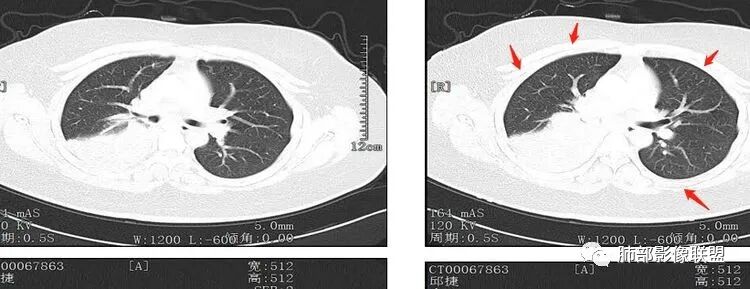

我们看看影像

先外周

其余区域干净

我再捋一捋支气管

右主支气管

上叶支气管

中间段

争议的地方这是上叶?中叶?

说实话图不全

关键点——中间段支气管堵塞处

没有显示

都是以肺内的病变为主

其实关键点在中间段支气管

断层面是没办法的情况,因为图太多,需要选择

各人看片的习惯不同,选的图像也不一样

通过视频显示中间段堵了

支气管腔内占位

远端低强化,提示粘液很多

纵隔淋巴结大